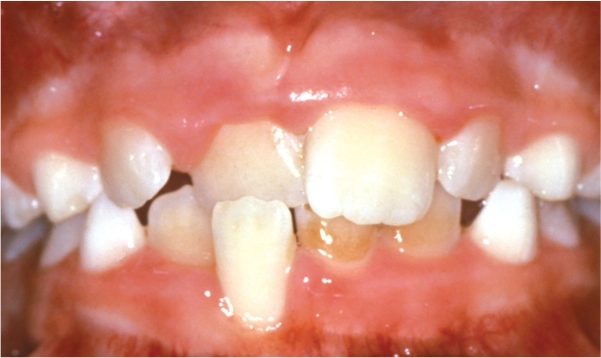

Ectopic Eruption

Ectopically erupting maxillary molar